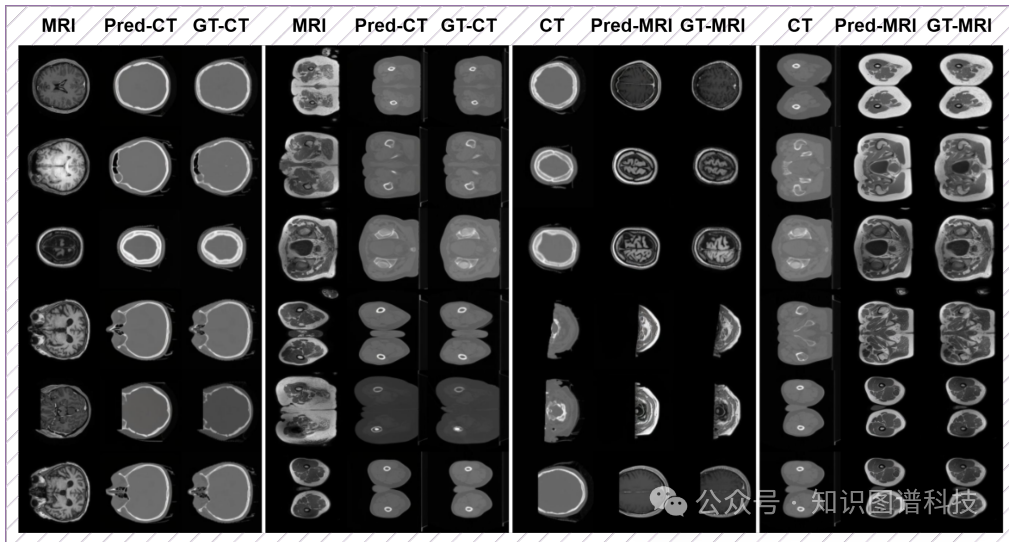

模态转换:在CT到MRI的脑部和骨盆区域的转换任务中,HealthGPT-M3的SSIM得分为79.38,显著优于传统方法。